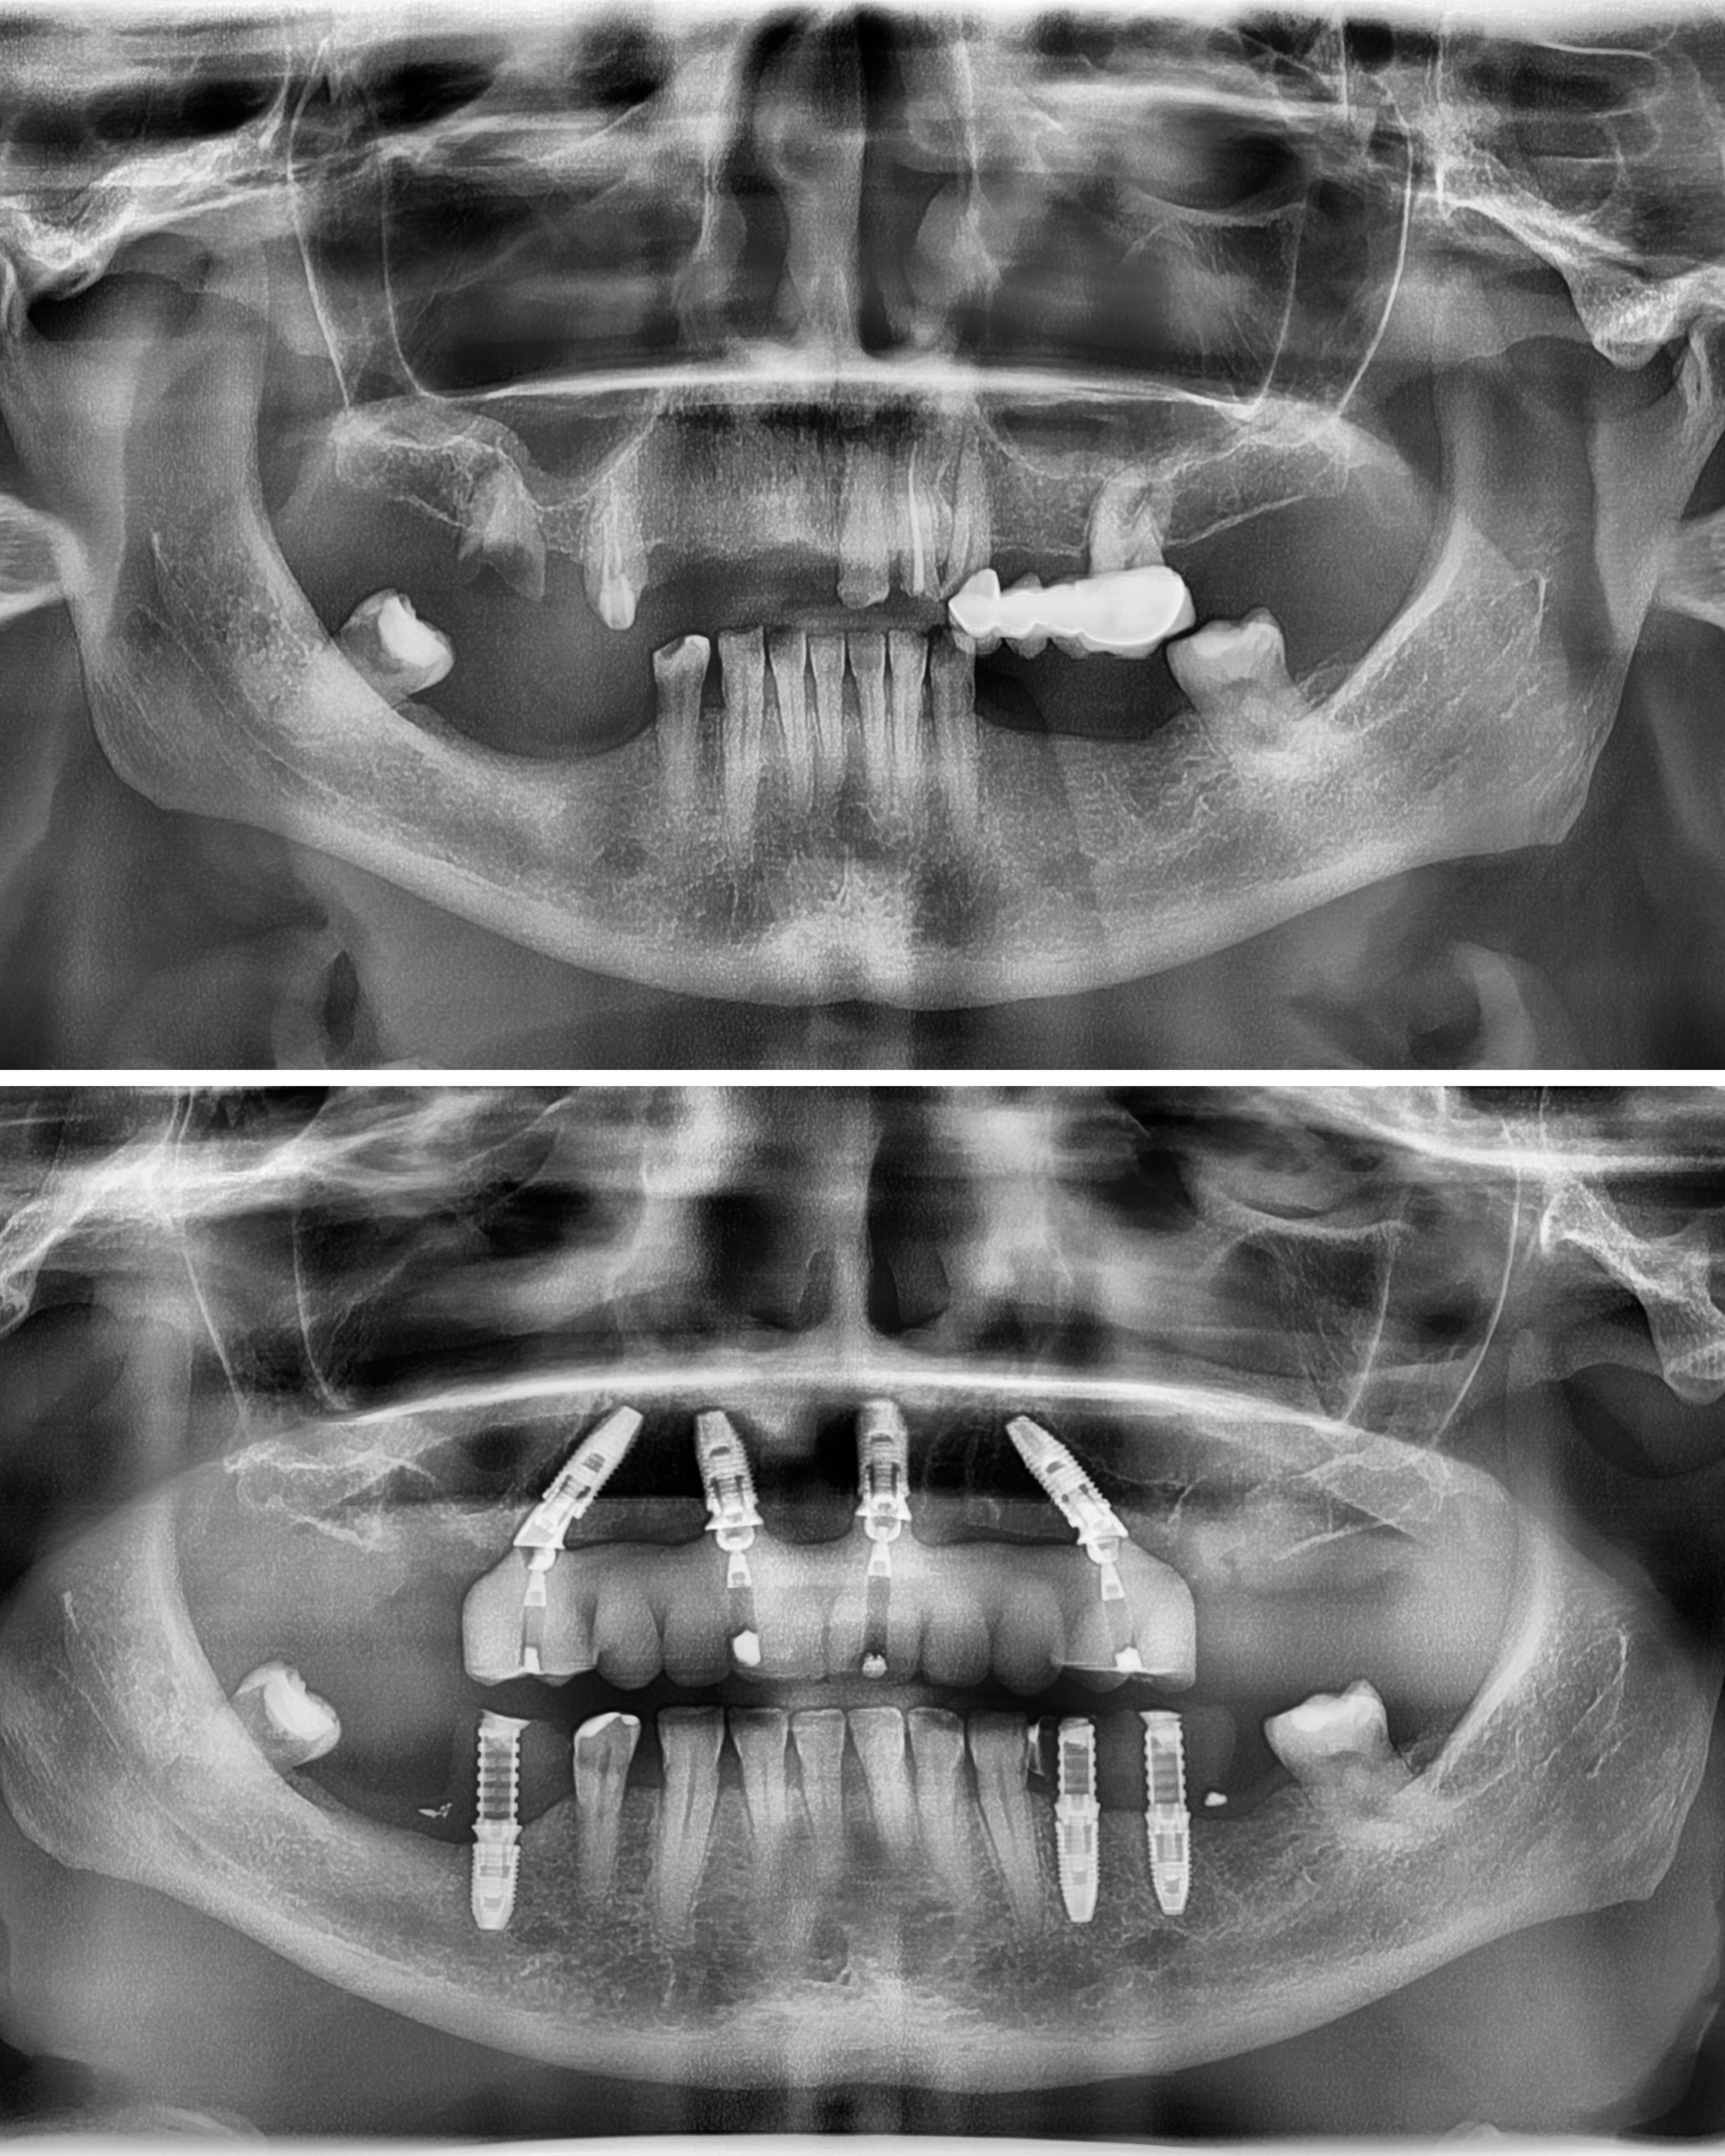

Po konsultacji w MALO CLINIC Warszawa i wykonaniu pełnej diagnostyki Pani Joanna została zakwalifikowana do leczenia metodą Malo Clinic Protocol.

Zabieg w Malo Clinic – nowe zęby w jeden dzień

Zespół specjalistów MALO CLINIC przeprowadził zabieg metodą Malo Clinic Protocol, obejmujący usunięcie zębów nienadających się do leczenia, wprowadzenie czterech implantów oraz zamocowanie stałego mostu tymczasowego MAAB (Malo All Acrylic Bridge™ tego samego dnia. Cały proces wykonano z wykorzystaniem technologii cyfrowej – fotogrametrii, planowania komputerowego i druku 3D – co zapewnia maksymalną precyzję i naturalny efekt odbudowy.